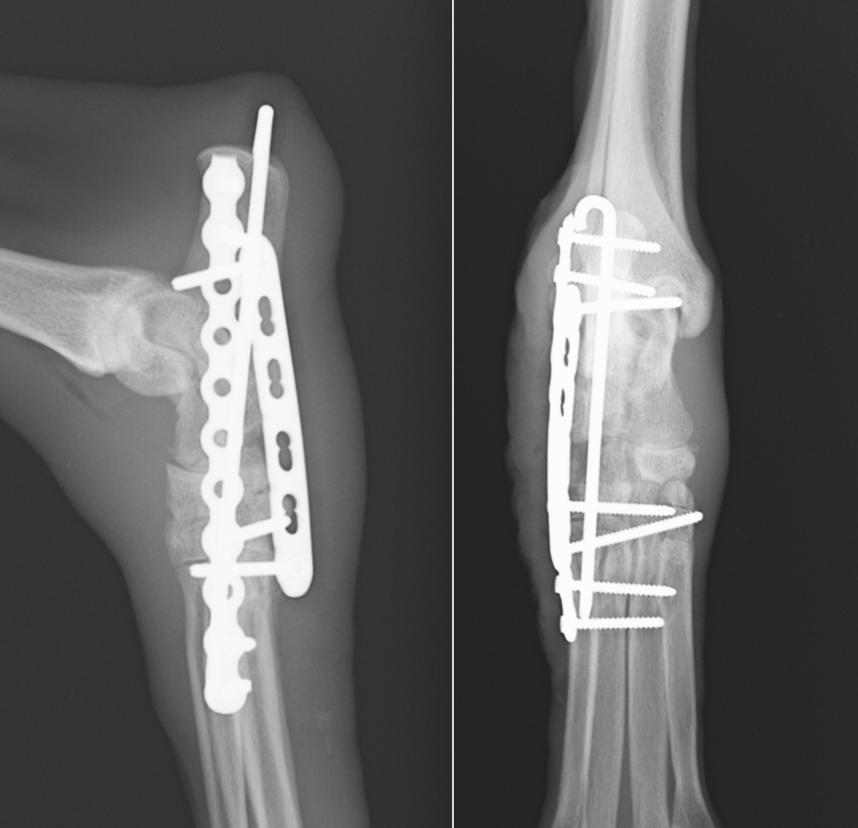

治療には骨の安定化、関節の安定化が必要となり、関節固定術が適応となります。脛骨と距骨の関節は問題なかったため、踵骨より遠位の固定のみを行いました。関節固定には強固な固定が必要となり、時間もかかるためロッキングプレートを使用し、髄内ピンも合わせて行いました。現在術後半年以上経ちますが経過は順調でどちらを治療したのかわからないレベルに回復しています。